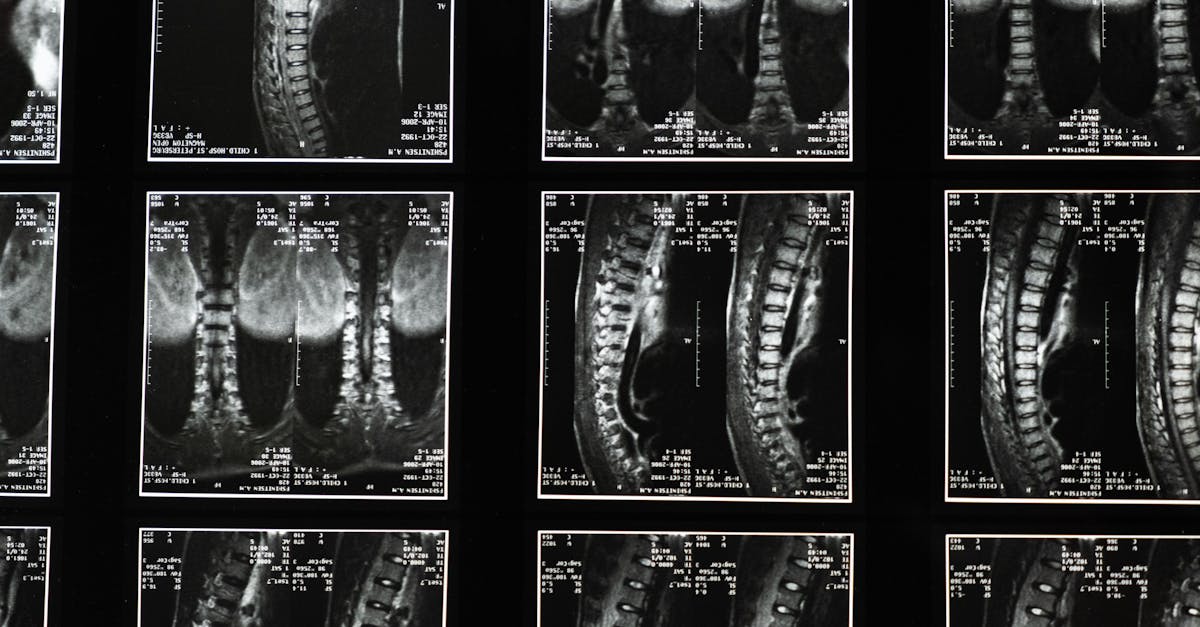

Commençons par le cas précis qui a déclenché l’alerte : une jeune femme s’est présentée à son rendez-vous d’IRM en laissant malencontreusement un plug anal contenant un noyau métallique à l’intérieur de son corps. Cet objet, conçu majoritairement en silicone mais intégrant un composant ferromagnétique, a interagi violemment avec le champ magnétique de l’appareil IRM. La technologie de l’IRM repose sur des impulsions magnétiques très puissantes capables de générer des images radiologiques nettes et détaillées.

Comprendre la technologie IRM et pourquoi elle amplifie les risques liés au métal

L’IRM utilise des champs magnétiques puissants associés à des ondes radio pour produire des images transversales précises des organes et tissus. Contrairement aux rayons X ou scanners, l’IRM ne fait pas appel à la radiation ionisante, ce qui en fait un choix de prédilection pour un large éventail d’examens médicaux. Cependant, cette technologie médicale est basée sur un principe physique qui interagit directement avec les propriétés magnétiques des matériaux.

Le professeur Adam Taylor, expert en anatomie humaine, souligne que la vitesse à laquelle de petits objets ferromagnétiques se déplacent à l’intérieur du champ magnétique peut atteindre jusqu’à 60 km/h. Dans le cas du sextoy oublié, ce déplacement a approché la vitesse du son, accentuant considérablement les risques physiques aux conséquences dramatiques.

Le lien entre la technologie IRM et la physique des matériaux métalliques justifie ainsi pleinement un protocole rigoureux de sécurité.